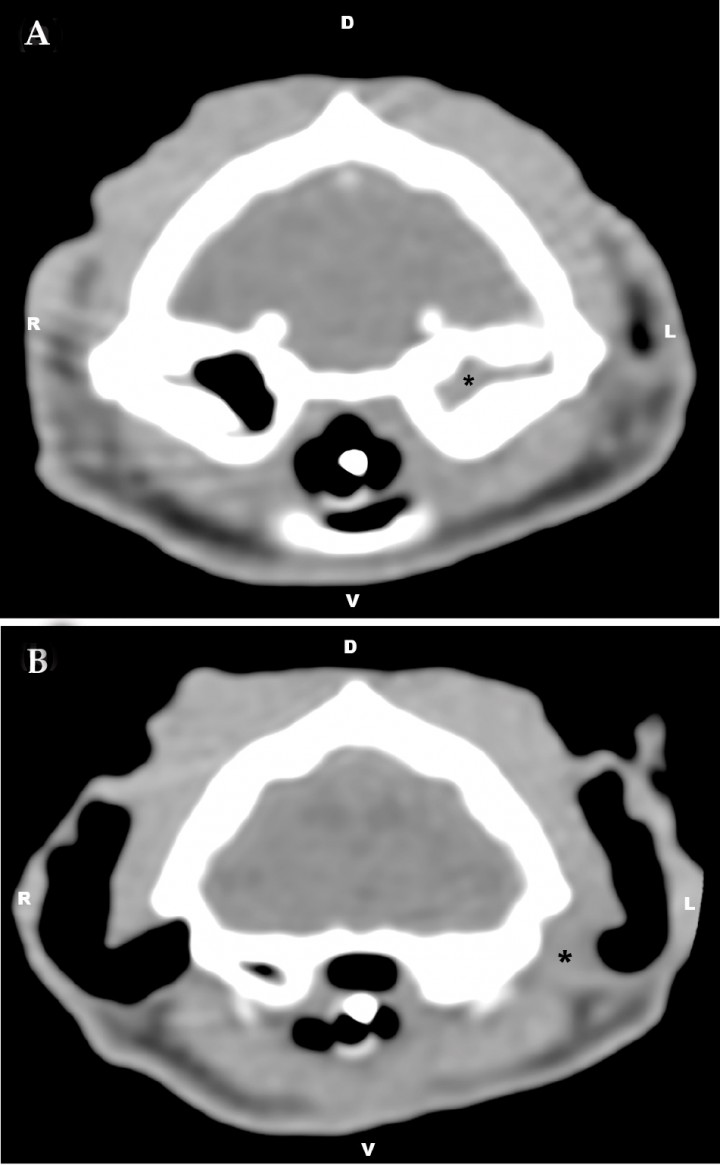

CT of the tympanic bullae was acquired under general anesthesia (GE HiSpeed Dual, GE Heathcare System, Wauwatosa, WI). CT technical parameters were as follows: helical acquisition, bone and standard algorithm, 120 kVp, 200 mAs, 0.6-mm slice thickness, pitch of 0.8, and 0.75 s/rotation. Reformatted images in sagittal and dorsal planes were obtained. The images were reviewed using a picture archiving and computer system (PACS) workstation and bone (window width [WW]= 2000, window level [WL]= 800) and soft tissue (WW=360, WL=60) window display settings. CT examination revealed an accumulation of soft-tissue dense material (65 Hounsfield Units) within the left tympanic cavity and the horizontal portion of the left external ear canal (Fig. 1). Mild sclerosis of the wall of the left bulla was noted (Fig. 2). These findings were consistent with left otitis media and externa.

<p>Transverse computed tomography image at the level of the tympanic bullae using soft tissue window (window width [WW]= 360, window level [WL]= 60). (A) Accumulation of soft-tissue dense material can be seen within the left tympanic cavity and (B) the horizontal portion of the left external ear canal (*). R= right, L= left, D= dorsal, V= ventral.</p>

Transverse computed tomography image at the level of the tympanic bullae using soft tissue window (window width [WW]= 360, window level [WL]= 60). (A) Accumulation of soft-tissue dense material can be seen within the left tympanic cavity and (B) the horizontal portion of the left external ear canal (*). R= right, L= left, D= dorsal, V= ventral.